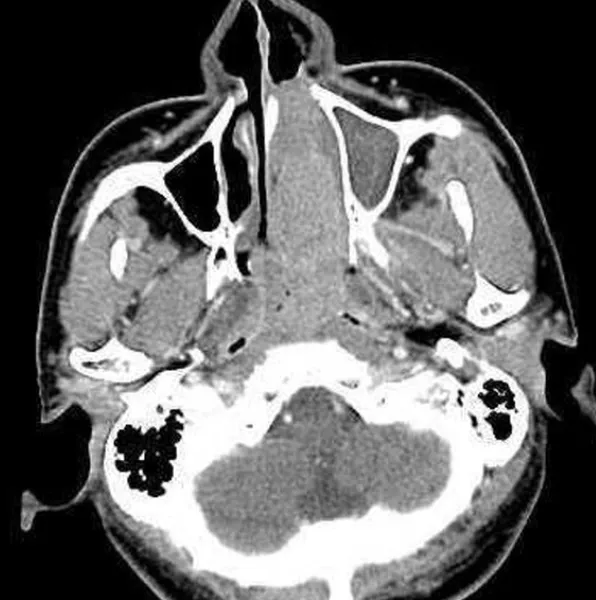

(비인두암의비강 내시경 사진과 CT 소견 (비인두에서 시작된 암이 코 안을 가득 메울 정도로 진행한 상태))